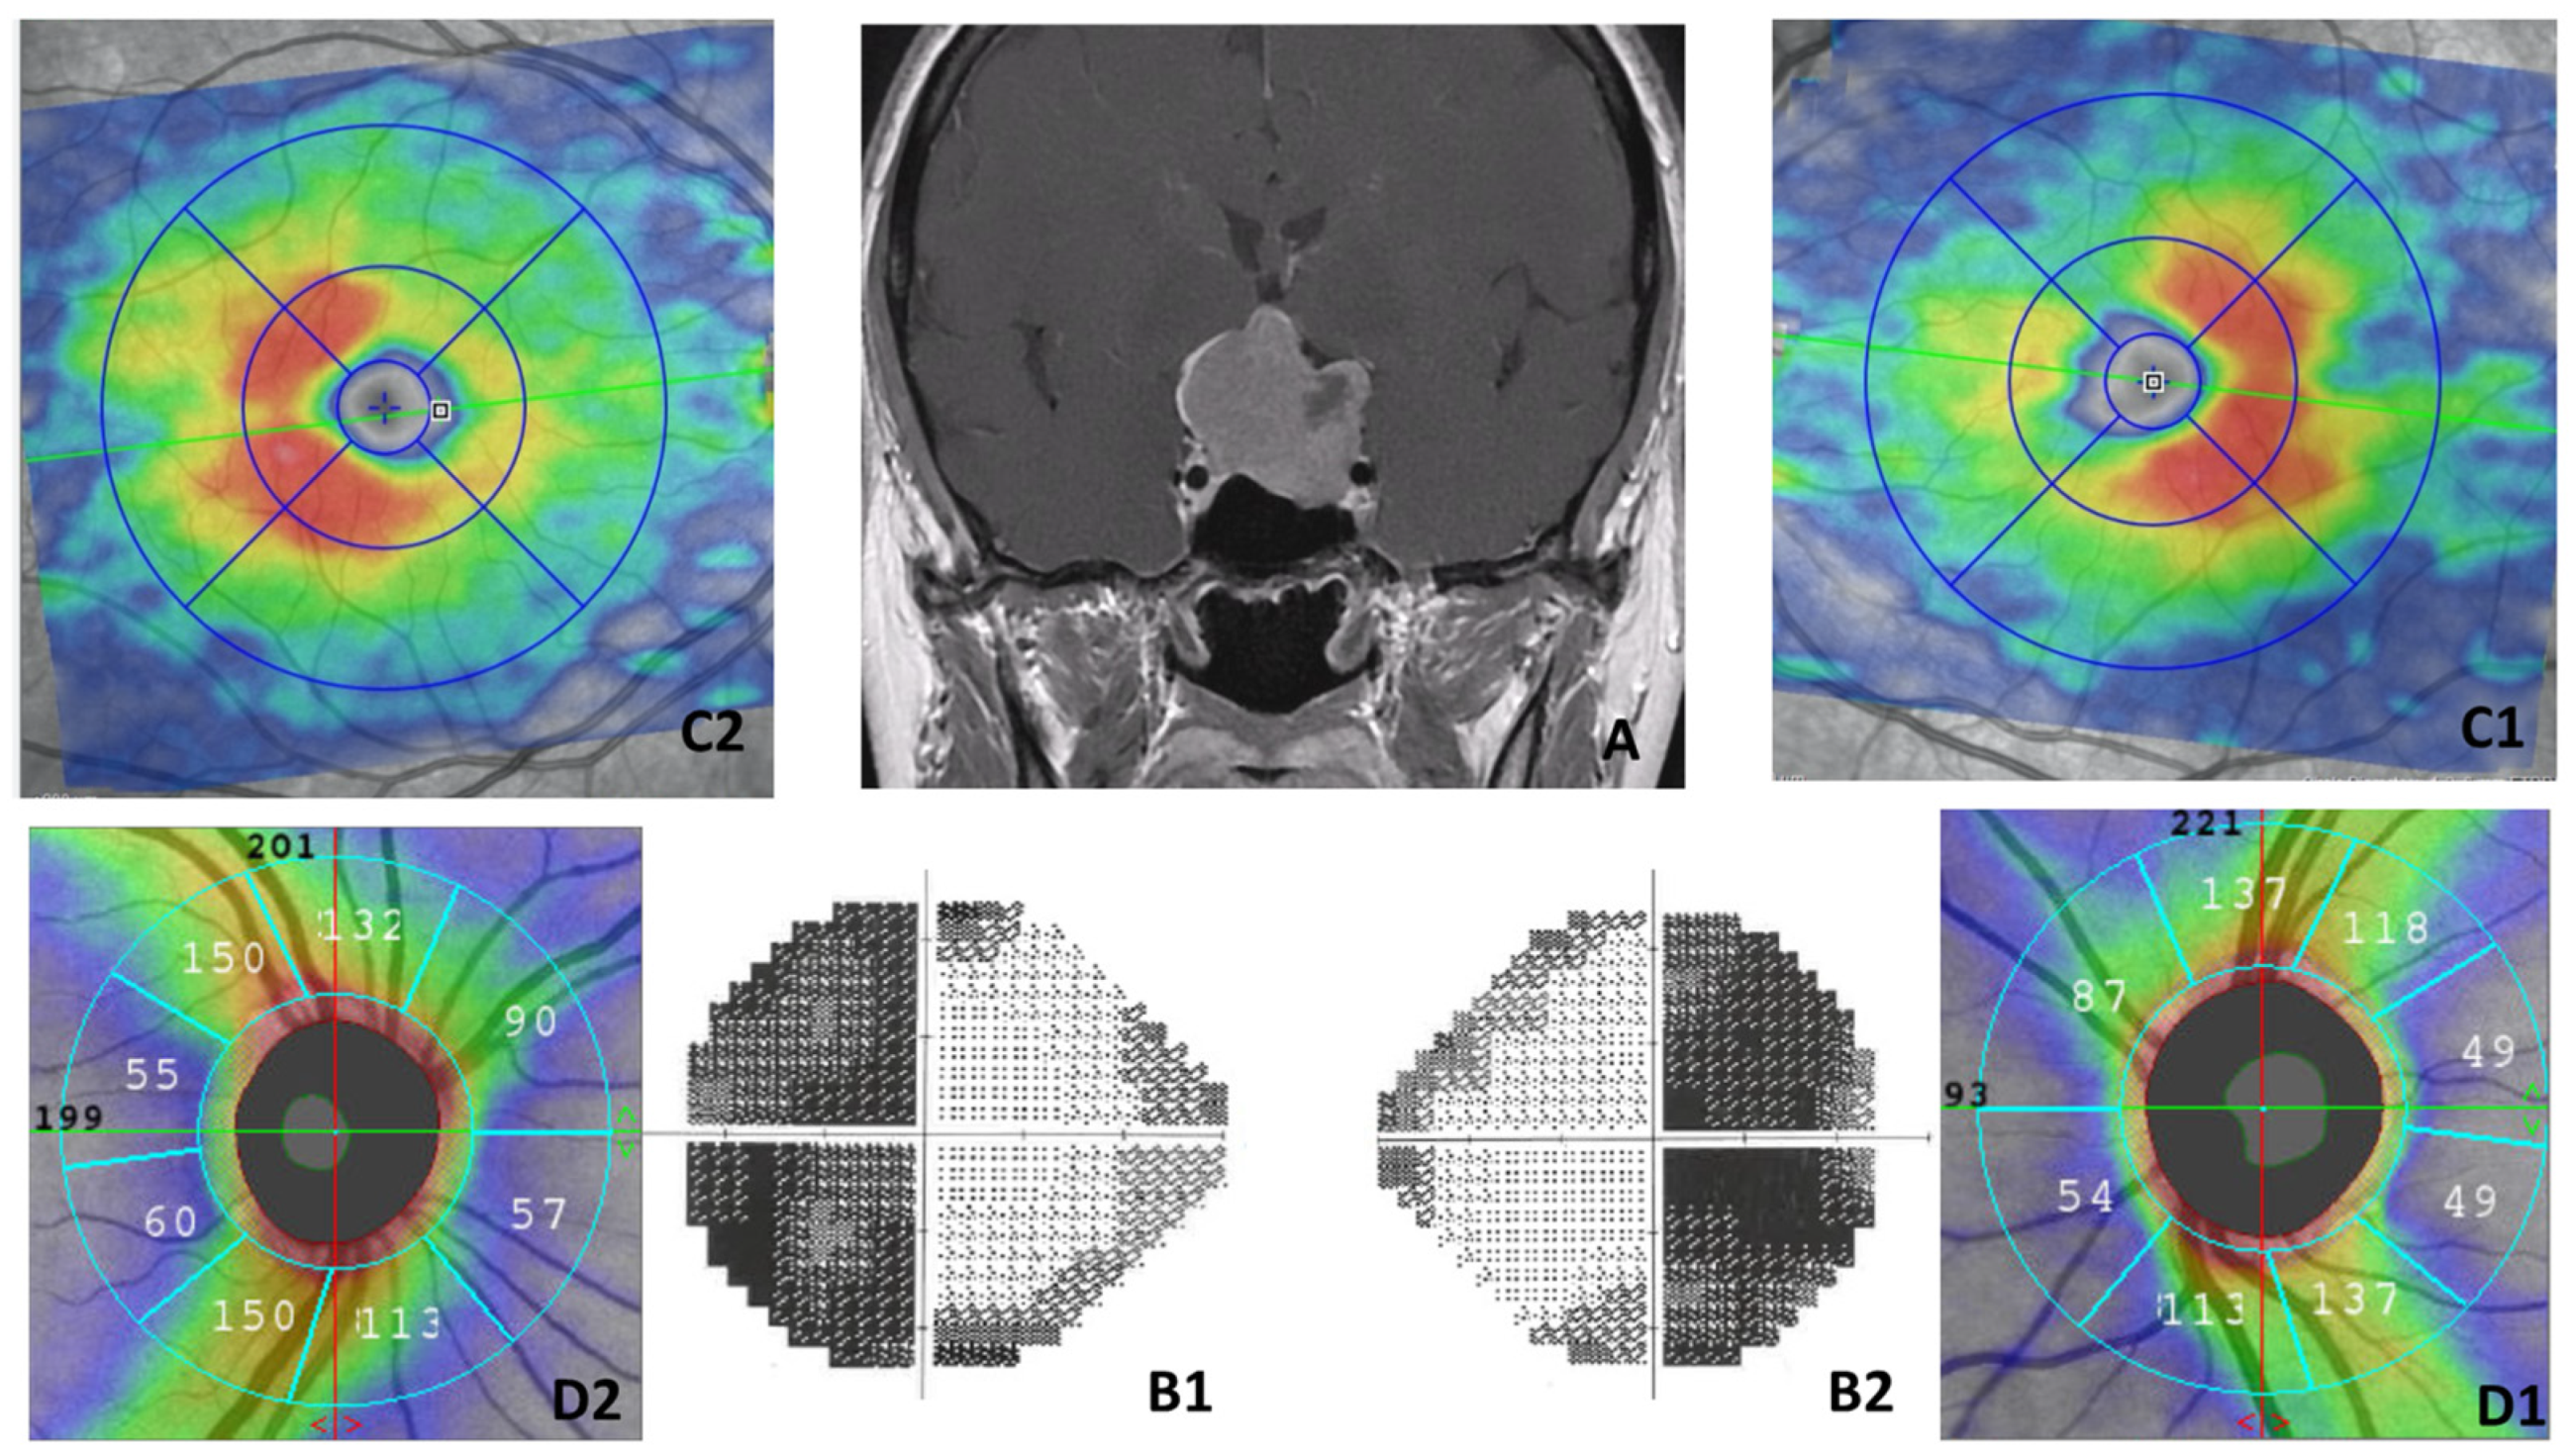

3.3. VF and SD-OCT Parameter Outcomes

3.4. OCT-A Parameter Outcomes

4.2. Main Results